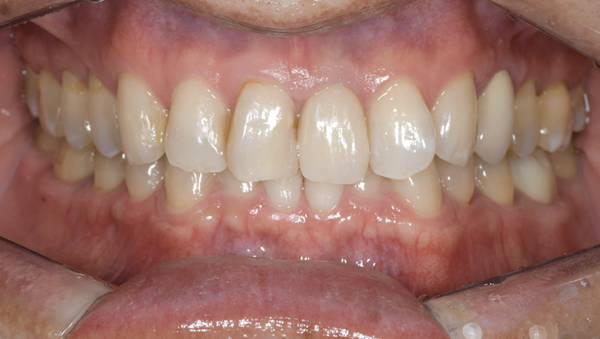

症例1

治療前

治療後

治療内容

口腔内の銀歯を全てセラミックにしたいというご希望でした。親知らずは抜歯しています。笑ったときや自然なスマイルをしたときも銀歯が見えなくなり自然になりました。

治療期間 約2ヶ月

治療費 合計:935,000円 (内訳)

オールセラミック:110,000円×5本

セラミックインレー:55,000円×7本

治療のリスク・副作用 銀歯の下で虫歯が大きくなっていたら歯の中の神経をとらないといけないことがあります。また、被せ物を外すと、ご自身の歯が少ない場合は別途はを残すための処置が必要になることがあります。